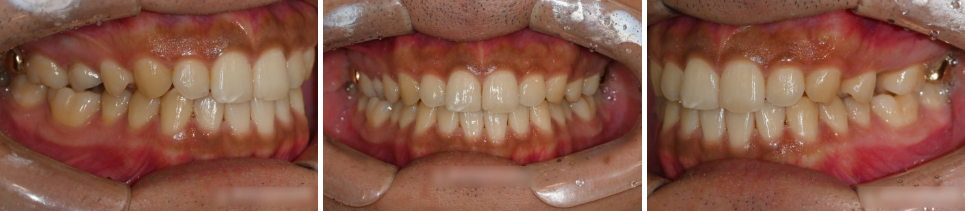

내원 당시 사진

언뜻 봤을 땐 치열이 고른편이라

‘교정이 꼭 필요한가?’ 싶을 수 있지만,

이 환자는 다른 부분이 있습니다.

당시, 위쪽 어금니 하나를

일찍 상실하여 임플란트 식립 예정인

상황이라는 점입니다.

그러나 이 상태가 꽤 오랜기간

방치가 되었는지 앞 어금니가 이동되면서

발치 공간이 줄어든 상태였습니다.